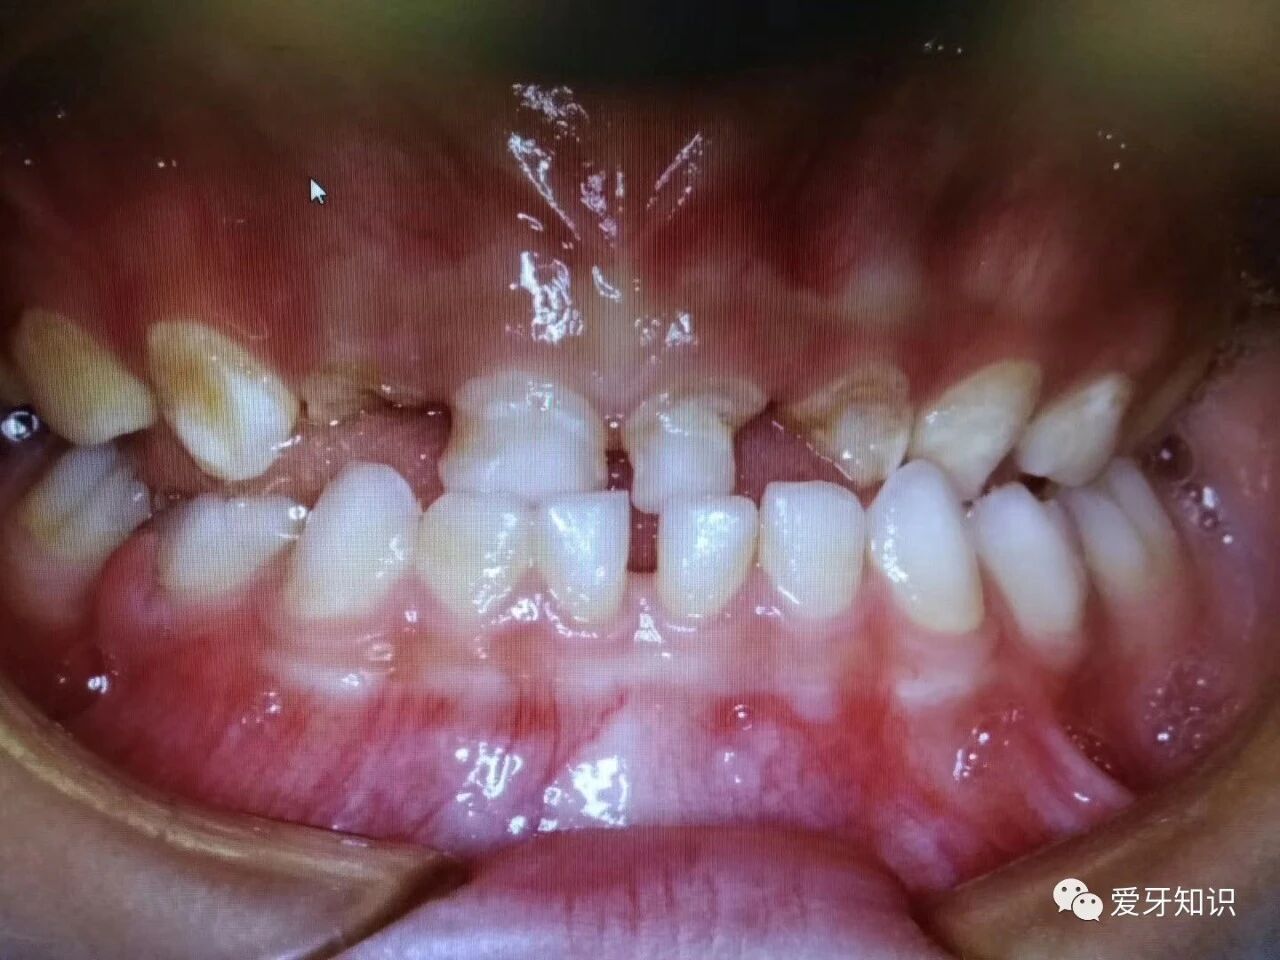

个别牙齿地包天。

前牙地包天。

当然开颌,龅牙,深覆颌,牙齿不齐拥挤,都可以早期干预矫正的。